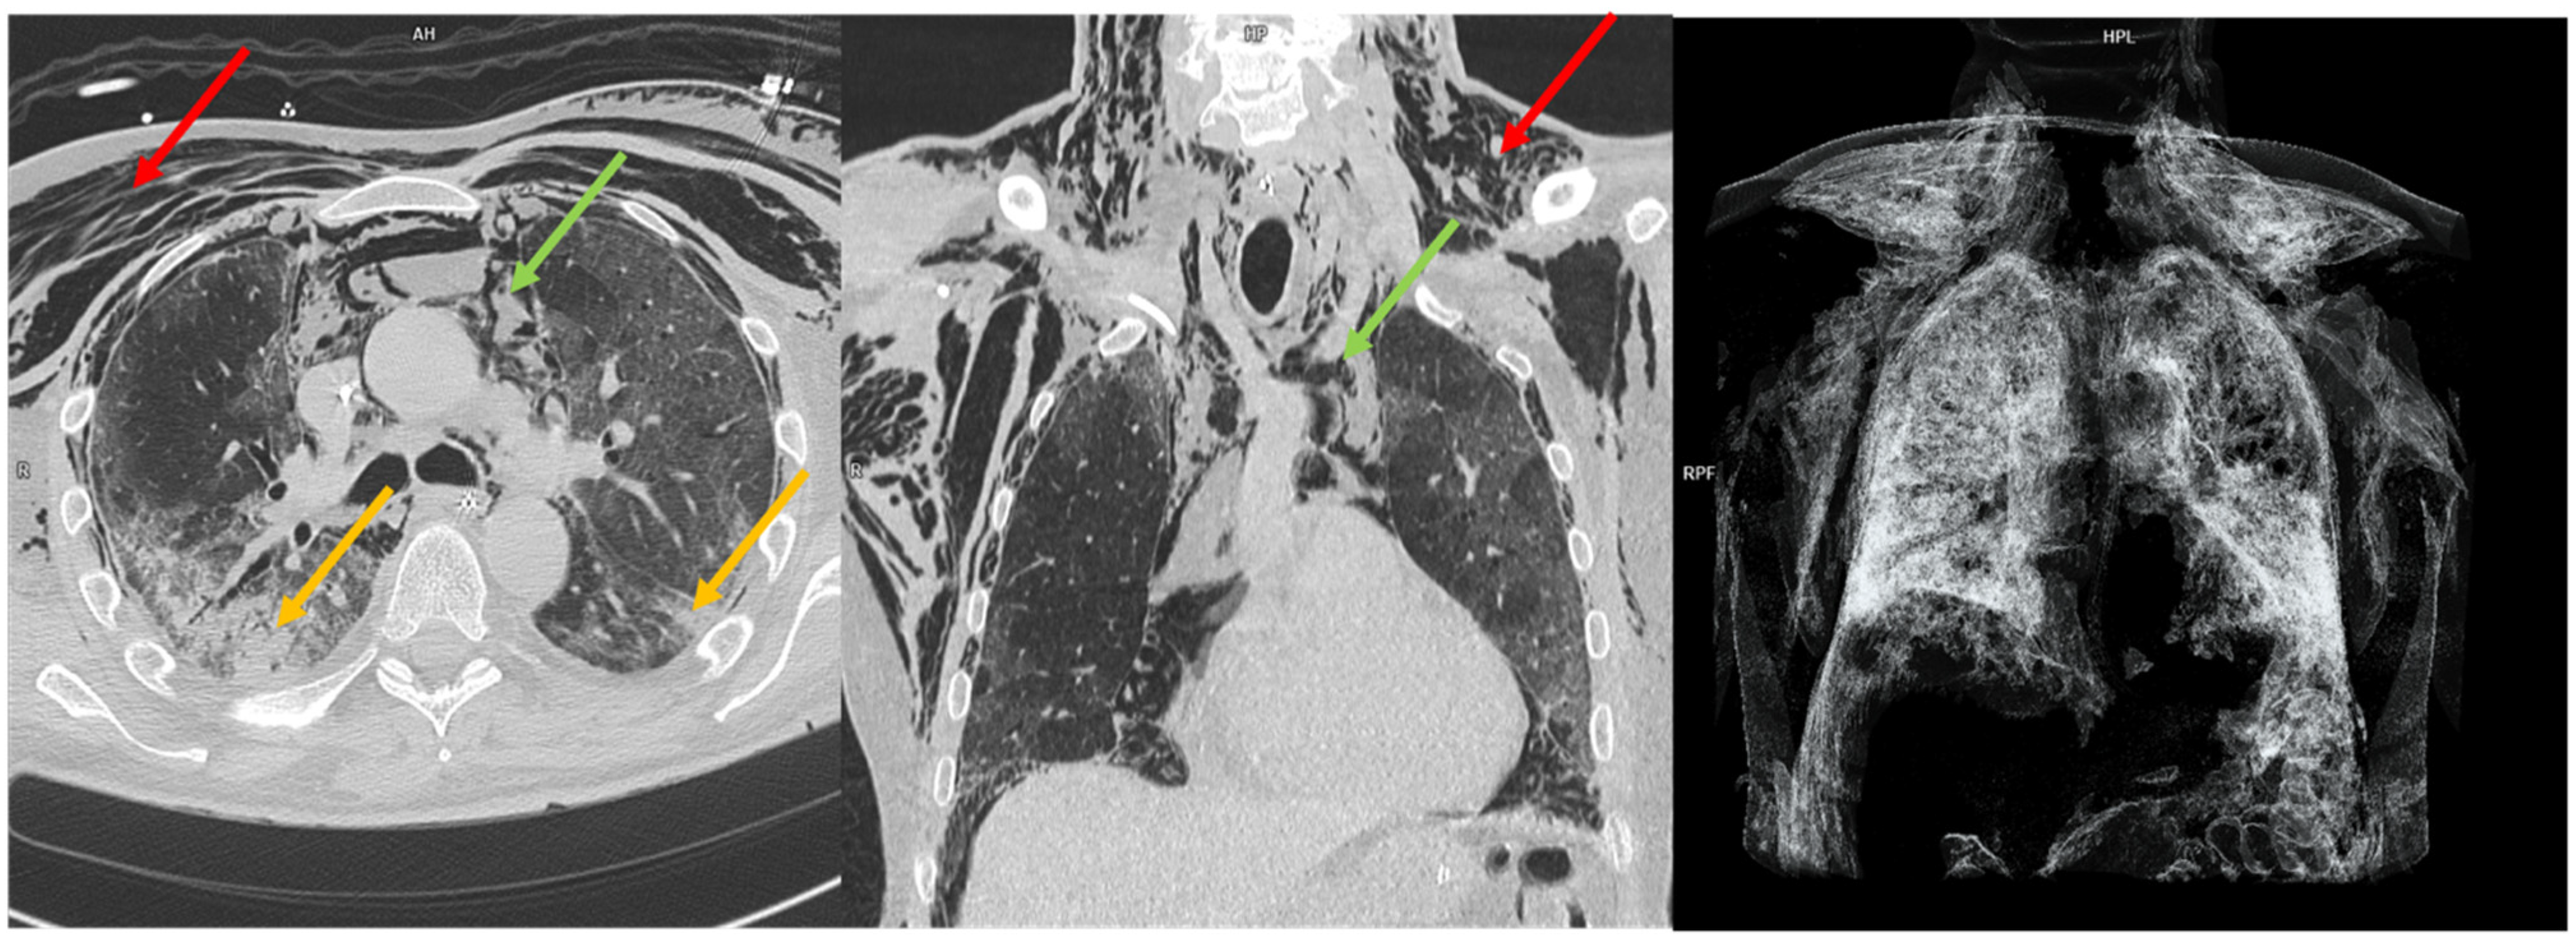

- Paternoster, G.; Belmonte, G.; Scarano, E.; Rotondo, P.; Palumbo, D.; Belletti, A.; Corradi, F.; Bertini, P.; Landoni, G.; Guarracino, F.; et al. Macklin Effect on Baseline Chest CT Scan Accurately Predicts Barotrauma in COVID-19 Patients. Respir. Med. 2022, 197, 106853. [Google Scholar] [CrossRef] [PubMed]